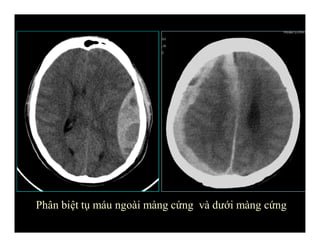

Phân biệt tụ máu ngoài màng cứng và dưới màng cứng

EDH